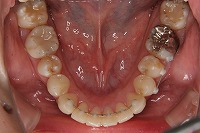

下顎

前歯が出ていて歯並びが悪い事を主訴に来院された、26歳1か月の女性です。診断「歯と歯槽基底の大きさの不調和による叢生」上顎は右側第1小臼歯と左側の犬歯、下顎は抜歯をせず治療を行いました。